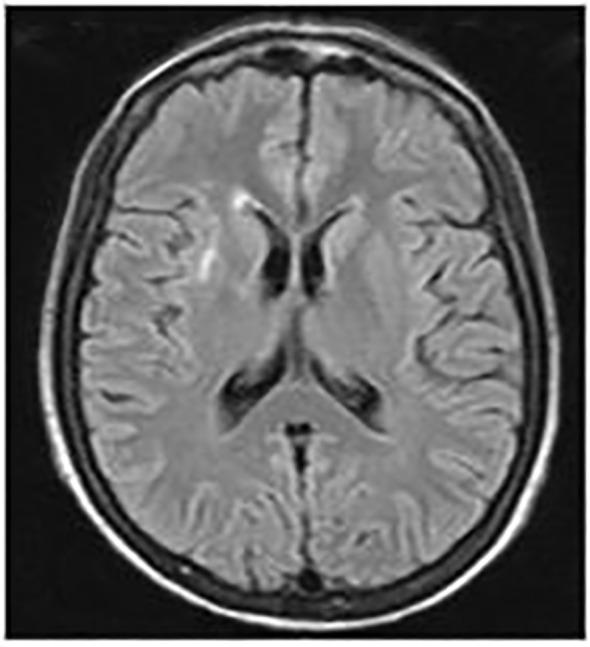

无菌性脓肿综合征是一种罕见但越来越被认识到的疾病,属于自身炎症性疾病范畴。在此,我们描述了一例患者,该患者出现腹痛和发热,伴有多个腹部和腹部外脓肿,且不存在潜在的血液学、自身免疫性、感染性或肿瘤性疾病。最初,患者对糖皮质激素有反应,但停药后经历了几次病情复发,导致开始使用肿瘤坏死因子α(TNFα)抑制剂进行治疗。5年后,尝试停药导致疾病再次发作。最终使用一种生物类似物TNFα抑制剂实现了缓解,尽管需要缩短输注间隔时间。